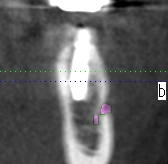

術後のCTになります

安全も確認して埋入しています